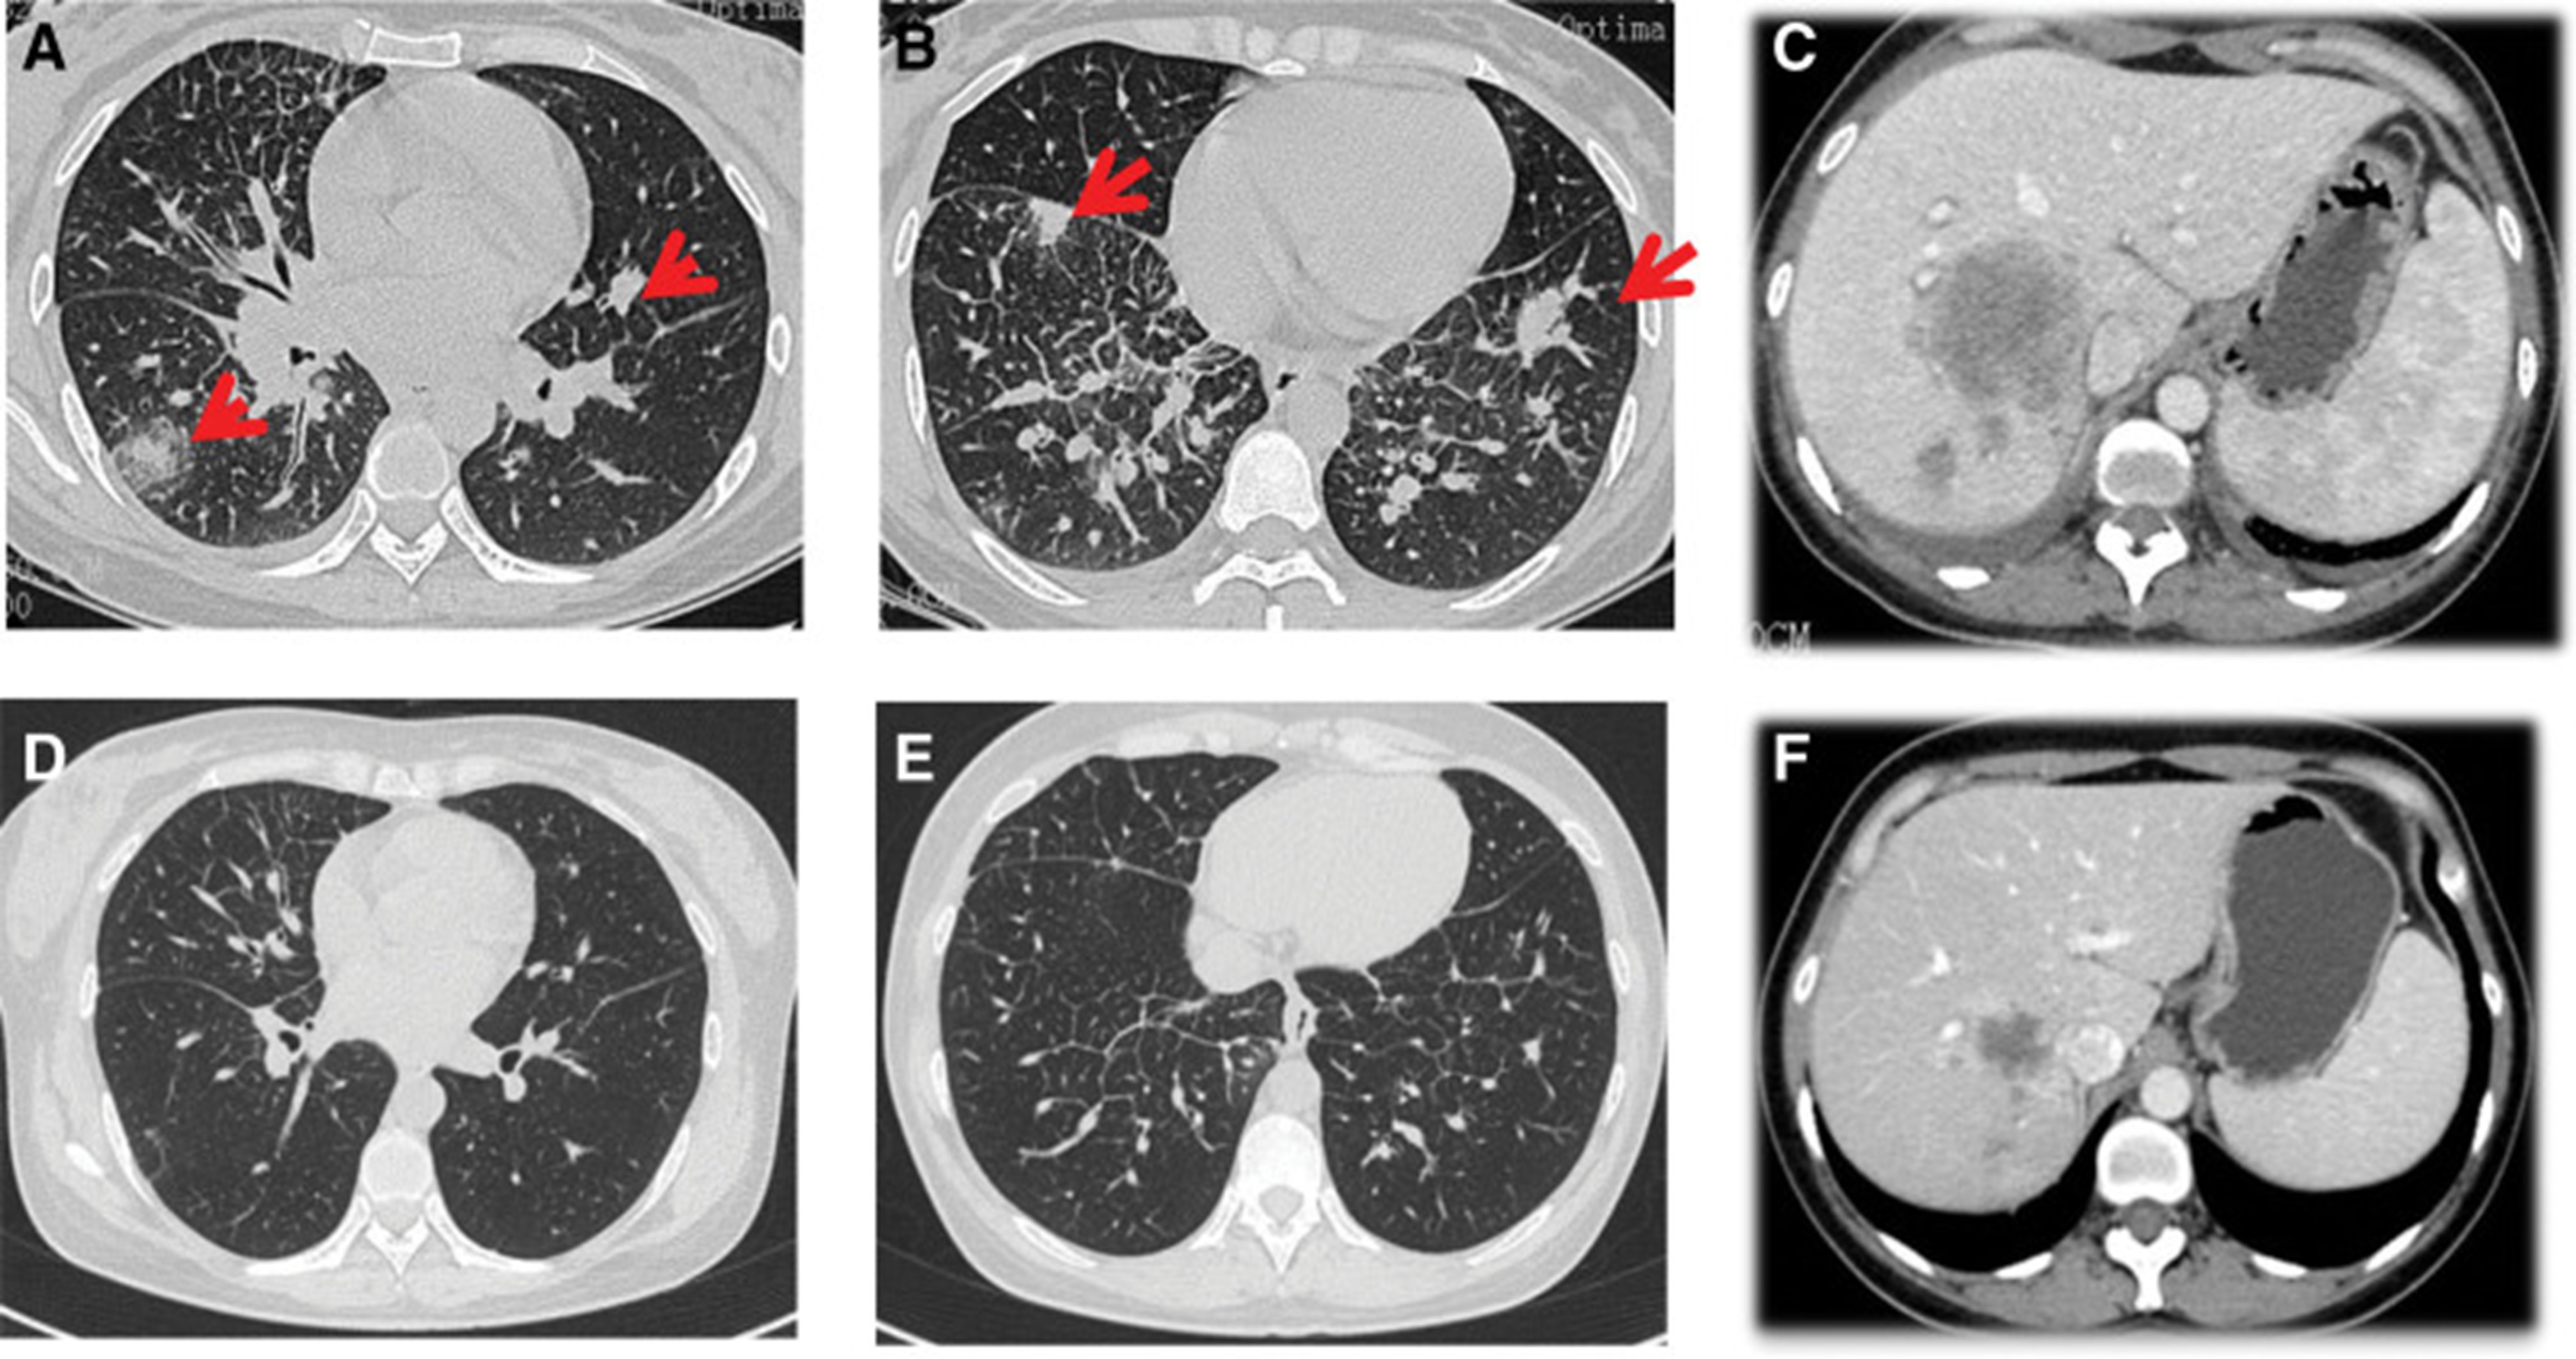

1个月后复查显示肺部和肝内病变进展(图1)。(图 6A-C)(根据RECIST1.1),她的抗肿瘤治疗改为“培姆曲塞加卡铂和贝伐单抗”的治疗一个周期。2020年12月至2021年1月,再次改变患者的治疗方案,这次改为“劳拉替尼联合达拉非尼”靶向治疗。使用 PD 联合胸部和腹部 CT 评估疗效(图 1)。(图 6D-F)(根据 RECIST1.1)。患者无法耐受化疗、靶向治疗、IO 治疗或任何其他积极的抗肿瘤治疗。这是因为患者的一般情况较差,包括发烧、腹痛和胆红素水平升高等症状。随后,给予患者静脉营养、镇痛等对症支持治疗。患者于 2021 年 2 月 4 日去世,总生存期(OS)为 10 个月。

和 2022 年 1 月 (D-F) 的 CT 扫描.jpg)

图 6:2020 年 11 月 (A-C) 和 2022 年 1 月 (D-F) 的 CT 扫描。CT = 计算机断层扫描。